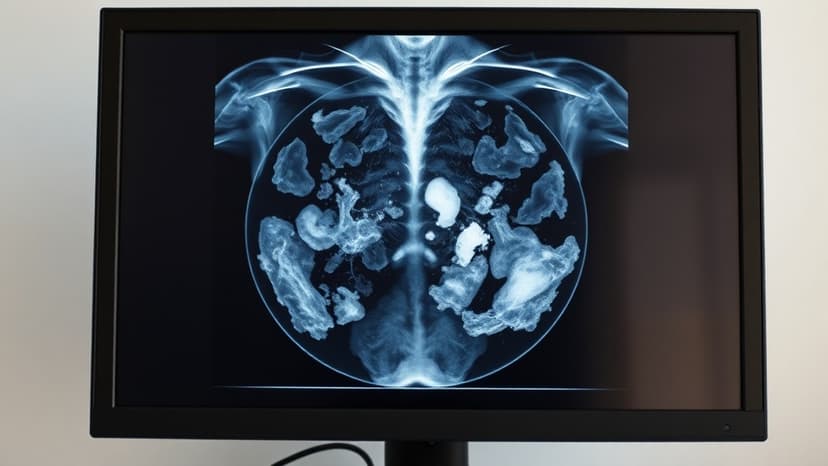

A routine mammogram recently led to an early-stage breast cancer diagnosis for Sarah Walton, a 53-year-old resident of Bingley. Ms. Walton expressed her shock at the diagnosis, particularly because she has no family history of the disease and could not feel any lumps.